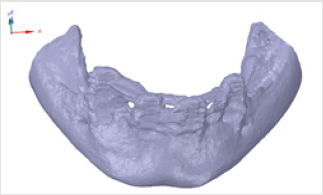

Subperiosteal implant design started with the processing of CBCT images. Figure 1 shows STL files of the patient’s mandibula, which is the lower jawbone. Figure 2 shows STL file of the patient’s maxilla, which is the upper jawbone. Figure 3 shows the result of virtual planning with the maxilla, mandibula, the designed implant, and denture. The final subperiosteal implant was designed based on CBCT images. Mechanical aspects were also considered in the design process of the titanium framework. Figure 4 shows the STL file of our titanium implant design with its three-dimensional geometry that had been analysed with finite element method.